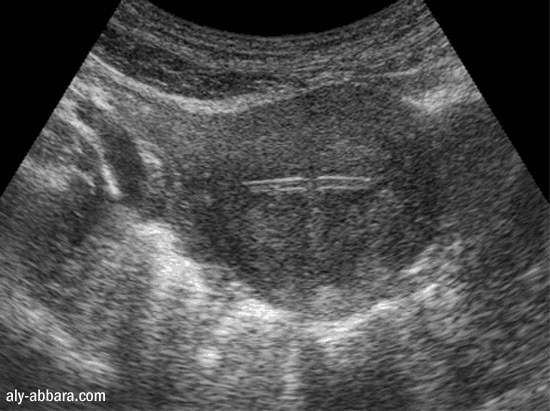

ou DIU (dispositif intra-utérin) hormonal

L'emplacement dans l'utérus vu par l'échographie

La branche horizontale du stérilet (coupe transversale sur l'utérus)

A comparer à l'aspect échographique du stérilet non hormonal